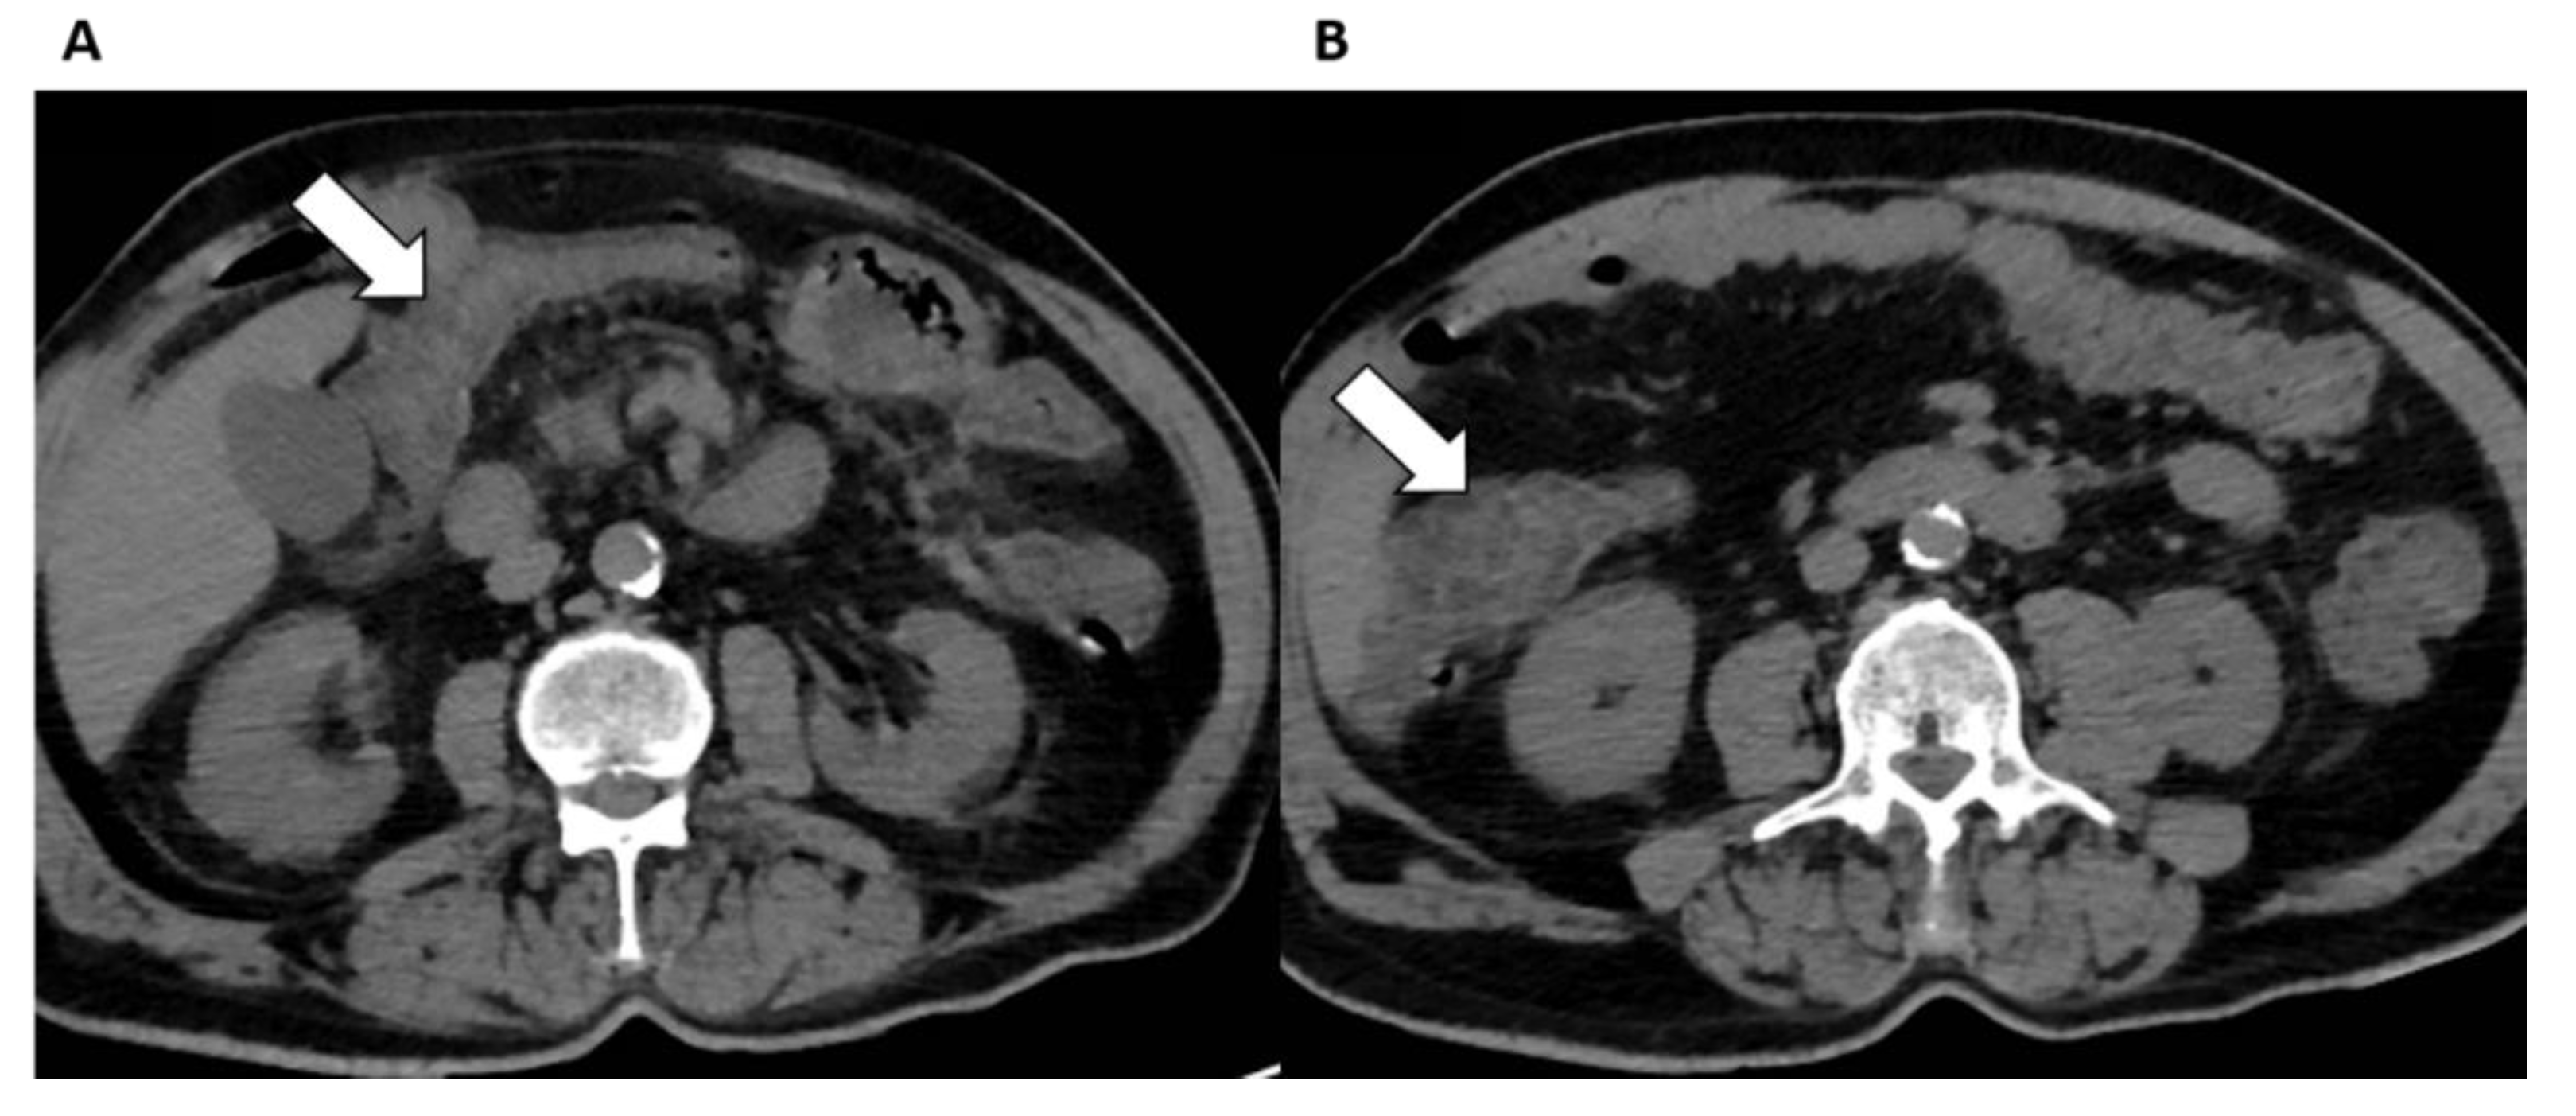

Kidneys

- Huang, Q.; Li, J.; Lyu, S.; Liang, W.; Yang, R.; Zhang, R.; Xiao, W.; Liu, J.; Yan, S.; Zheng, L.; et al. COVID-19 associated kidney impairment in adult: Qualitative and quantitative analyses with non-enhanced CT on admission. Eur. J. Radiol. 2020, 131, 109240. [Google Scholar] [CrossRef]

- Añazco, P.H.; Balta, F.M.; Córdova-Cueva, L. Bilateral renal infarction in a patient with severe COVID-19 infection. J. Bras. Nefrol. 2021, 43, 127–131. [Google Scholar] [CrossRef] [PubMed]

- Mui, L.W.; Lau, J.F.; Lee, H.K. Thromboembolic complications of COVID-19. Emerg. Radiol. 2020, 28, 423–429. [Google Scholar] [CrossRef] [PubMed]